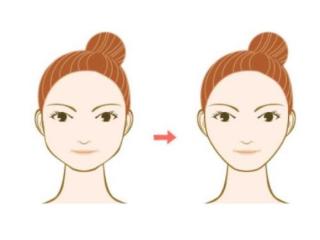

如果没及时治疗,炎症会向舌侧和颊侧扩散,引起吞咽疼痛,张口受限,面颊部肿胀,颌下淋巴结肿大等。

直观的讲,就是每一次吞咽都痛苦万分,嘴不能张大,面部肿大,像被家暴了一样。